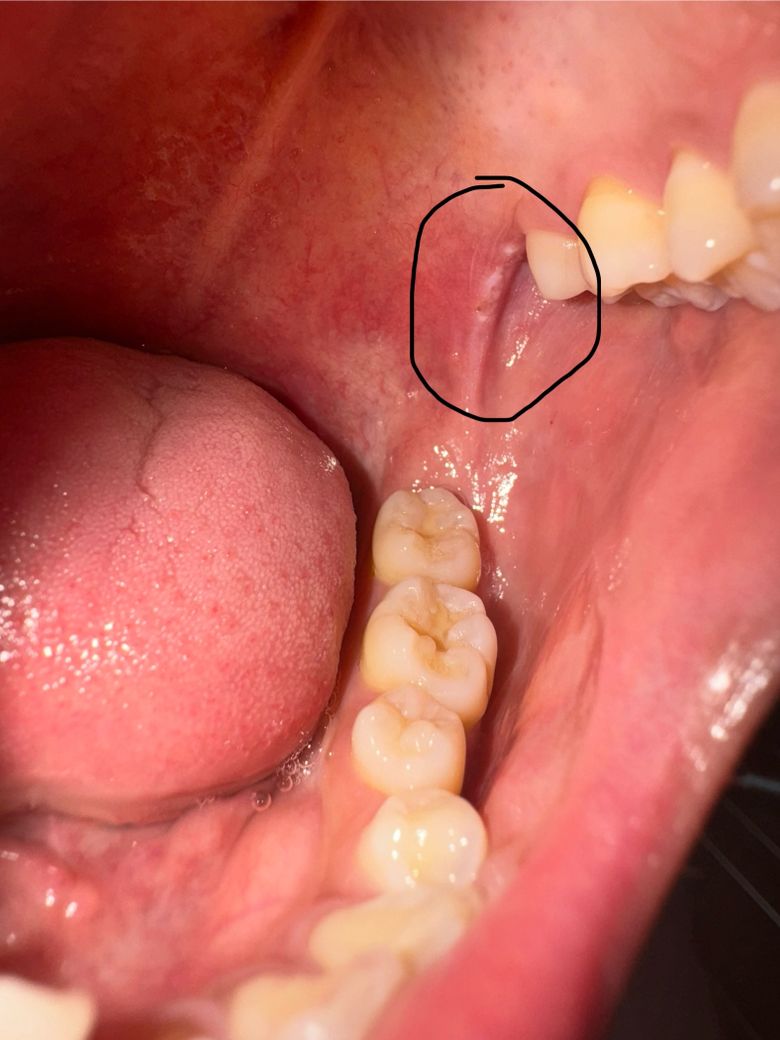

이 세 사진은 알보칠 바르고 두 시간정도 지난 사진입니다.

• 3번 째 사진

• 4번 째 사진

• 사진상으로 봤을때 익돌하악봉선부위 궤양성 염증의 양상이 있습니다. 그래서 입을 벌릴때 자극이 되어 통증이 유발될 수 있고요. 구강내과에서 정확한 검진을 받아보시기 바랍니다.

• 사진상으로 암의 형태일 가능성은 낮습니다. 만약 해당부위에 통증 및 붓기가 지속되는 경우에는 문제가 됩니다. 보다 정확한 확인을 위해 치과 진료를 받아보길 권합니다.